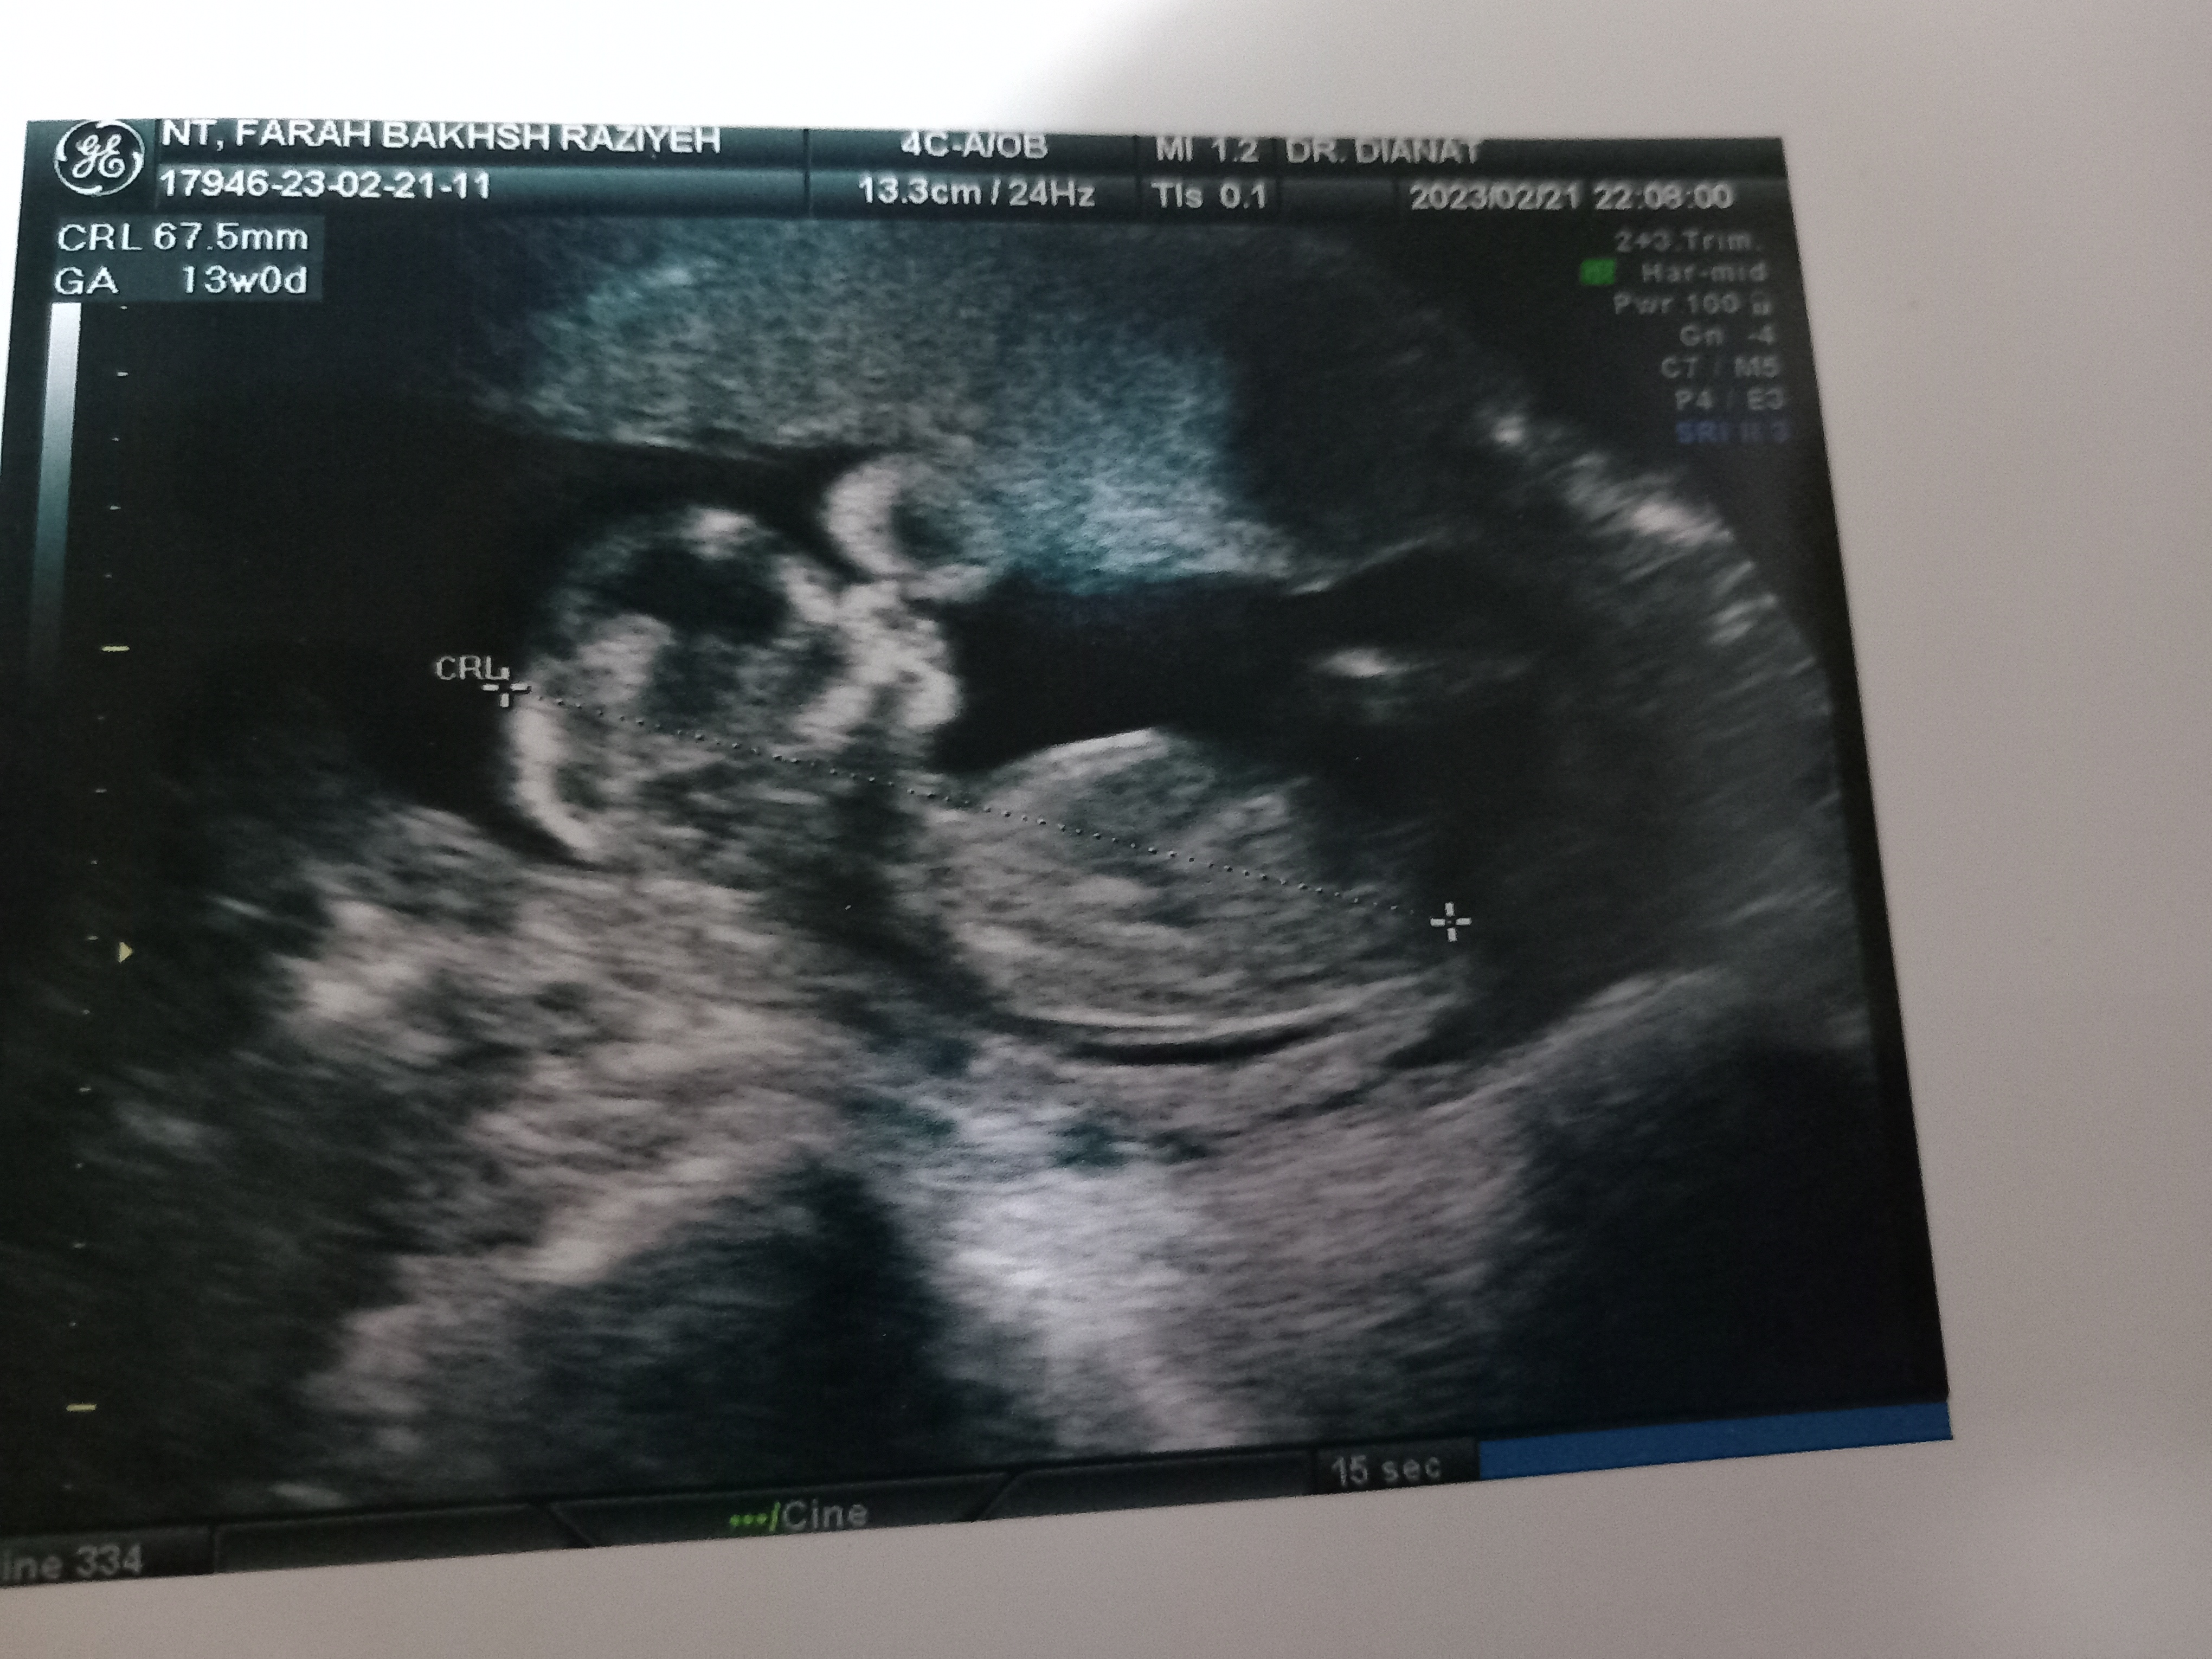

ووووو چه ماشالا موش چوچولو ام هست خدا حفضش کنه با این که هس ششم میگه پسره ولی توی عکس انگار داره میگه من دخترم. ولی ایشالا به حق همین ماه عزیزم خدا قسمت همه بکنه قسمت منم بکنه ایشالا سالم باشه اصلا دختر باشه، پسر باشه فرق نداره